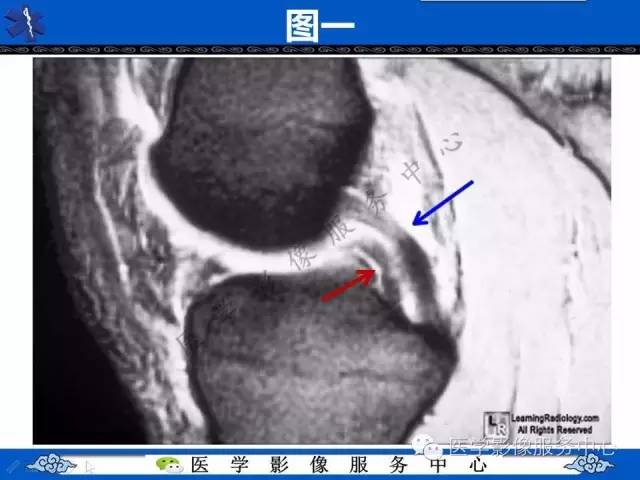

【影像征象】双后交叉韧带征